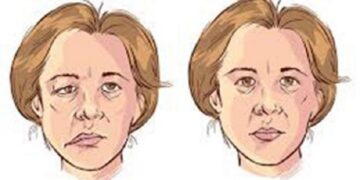

Read moreহার্টবিট ডেস্ক হঠাৎ মুখ বেঁকে যাওয়া এক ধরনের প্যারালাইসিস। যা মুখমণ্ডলে মানুষের সৌন্দর্য নষ্ট হয়ে যায়।এটা এক ধরনের স্নায়বিক সমস্যা...